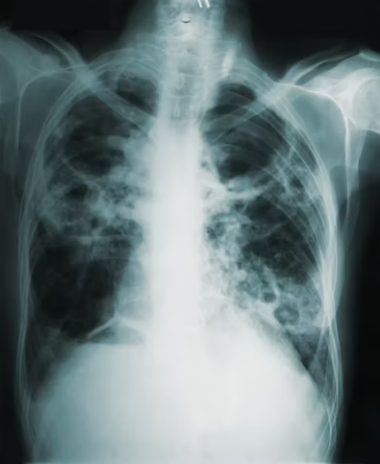

결핵 감염을 확인하기 위해 다양한 검사가 가능합니다. 투베르쿨린 피부 검사(TST) 또는 Mantoux 검사는 소량의 정제된 TB 단백질을 피부에 주사하는 것과 관련이 있으며 반응은 48-72시간 후에 평가됩니다. 또는 인터페론-감마 방출 분석(IGRA)과 같은 혈액 검사가 결핵 감염을 감지하는 데 도움이 될 수 있습니다. 이러한 검사에서 감염 가능성이 나타나면 추가 조사가 필요합니다. 흉부 X-레이와 같은 영상 검사는 폐의 이상을 밝힐 수 있는 반면, 가래 검사는 결핵균의 존재를 확인하기 위해 기침으로 생성된 점액 샘플을 분석하는 것과 관련됩니다.